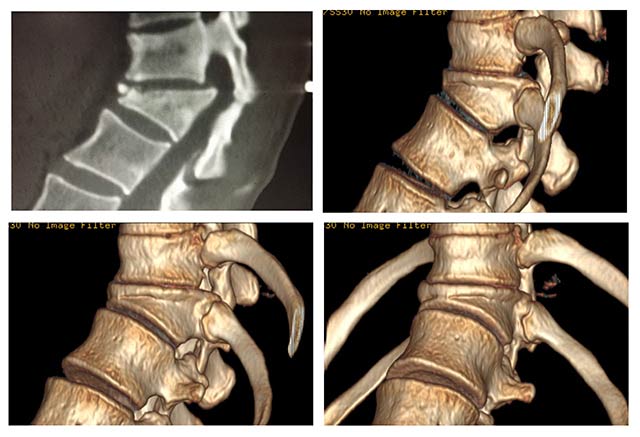

近日,新會區(qū)中醫(yī)院收治的一位病人劉阿姨,外傷后出現(xiàn)了頑固性腰背痛,每到打風(fēng)下雨的季節(jié)就痛得更加明顯了,曾在當(dāng)?shù)囟喾角筢t(yī)治療效果不理想,對她的生活帶來了很大的困擾。到底是怎么原因引起的頑固性腰背痛呢? 原來劉阿姨一年前因在4米高的地方跌下來導(dǎo)致腰椎骨折。因?yàn)樵诋?dāng)?shù)鼗緵]做過正規(guī)治療,遺留下了脊柱后凸畸形,從此就出現(xiàn)了腰背部頑固性疼痛。劉阿姨一家人通過多方打聽,在今年9月初來到了新會區(qū)中醫(yī)院骨一科求診。接診的梁惠林副主任醫(yī)師詳細(xì)地詢問了病情,并通過CT三位重建等檢查后認(rèn)為劉阿姨的腰背部頑固性疼痛是因?yàn)榧怪笸够我疖|體矢狀面喪失平衡及腰椎代償過度前凸引起的,術(shù)前測量Cobb角為45度,并且無神經(jīng)系統(tǒng)癥狀,手術(shù)是唯一有效辦法。劉阿姨這時候才知道打針和吃藥都解決不了的腰背痛的真正原因。梁醫(yī)生考慮到這個手術(shù)創(chuàng)傷大、技術(shù)復(fù)雜、風(fēng)險(xiǎn)高,本著對患者負(fù)責(zé)的理念,在手術(shù)前特別請到了廣州軍區(qū)總醫(yī)院馬向陽教授進(jìn)行遠(yuǎn)程會診,專門針對劉阿姨的情況設(shè)計(jì)了名為“PSO截骨矯形術(shù)”的術(shù)式。 2015年9月13日,經(jīng)過梁醫(yī)生和其助手歷時4小時緊張而細(xì)致的手術(shù),劉阿姨的脊柱畸形終于得到了解決,并因手術(shù)方式的改良大大減少了術(shù)中的出血和創(chuàng)傷,減少了劉阿姨的康復(fù)時間和身體負(fù)擔(dān)。術(shù)后復(fù)查X光片可見脊柱畸形的情況得到了矯正,術(shù)后Cobb角僅殘留4度。至9月24日出院時止,劉阿姨已經(jīng)可以扶拐下地活動,腰背痛得到緩解。

上為圖1,劉阿姨術(shù)前應(yīng)用新會區(qū)中醫(yī)院新16排螺旋CT三維顯像